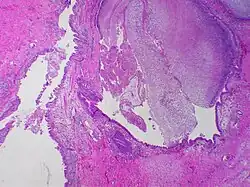

![]() | Vesicular mole | Micrograph of vesicular mole showing oedematous chorionic villus with circumferential proliferation of trophoblasts. | Category: Histopathology of chorionic villi | chorionic villi |